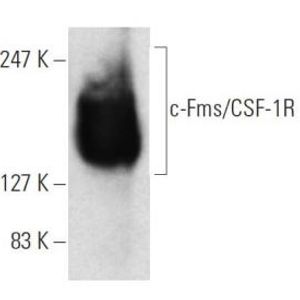

APR 22, 2016Health & MedicineMacrophages exist in every type of body tissue, in the lungs as alveolar macrophages and in the liver as Kupffer cells. ...